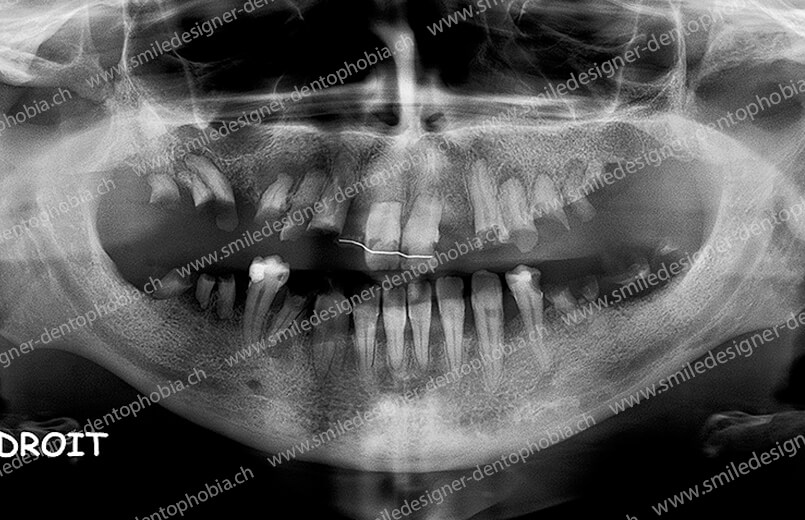

Cas clinique « DOMINO SURGERIES MCI » : Bridge implanto-porté sans extension postérieure (ALL ON 10/8). Version définitive des bridges avec un cosmétique en céramique. Double comblements de sinus et double greffes osseuses d’apposition pour la reconstruction du maxillaire.

Cas clinique « DOMINO SURGERIES MCI » : Bridge implanto-porté sans extension postérieure (ALL ON 8/6). Version définitive des bridges avec un cosmétique en céramique. Double comblements de sinus et double greffes osseuses d’apposition pour la reconstruction du maxillaire.

Cas clinique « DOMINO SURGERIES MCI » : Bridge implanto-porté avec extensions postérieures (ALL ON 6/6).